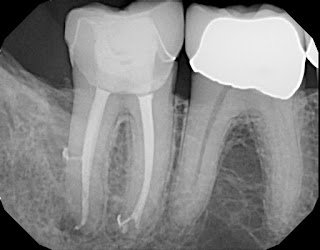

I have included several radiographic that demonstrate the “Thrill of the Fill” routinely seen at SSE using sonic activation of irrigating solutions. After our hands on demonstration with the GentleWave, I began putting aside radiographs after using sonic activation and found that the fill results were equally impressive.